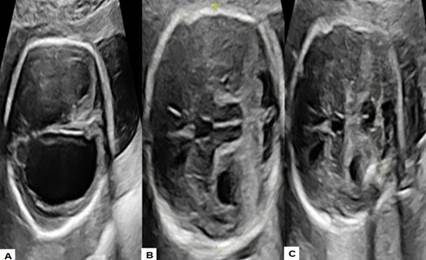

Figura 1 Hallazgos ecográficos del síndrome de Walker-Warburg. A) Ventriculomegalia bilateral con una banda hiperecogénica rodeando las estructuras supratentoriales y cuerpo calloso displásico. B) Desplazamiento del vermis hipoplásico y deforme. C) Lóbulos cerebelosos separados con alteraciones de estructuras vermianas.

La ecografía realizada en la consulta de alto riesgo obstétrico a las 24 semanas de gestación mostró un aumento en el tamaño de los ventrículos laterales, acompañado de una banda ecogénica que rodeaba las estructuras supratentoriales, y un cuerpo calloso corto y displásico. Además, se observó un desplazamiento del cerebelo y del tronco encefálico, ambos hipoplásicos y rotados debido al efecto de masa generado por los hemisferios cerebrales. Los lóbulos cerebelosos estaban separados y presentaban alteraciones estructurales (figura 1), estableciendo la posibilidad diagnóstica de SWW. La evaluación cardiaca fetal no evidenció anomalías. Los movimientos fetales observados eran aparentemente normales. Los estudios doppler realizados en las arterias uterinas maternas, umbilical y cerebral media fetal estuvieron dentro de los límites normales. Los padres optaron por no realizar pruebas genéticas invasivas.